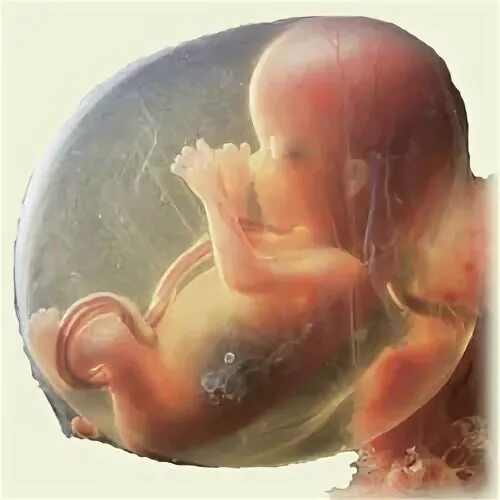

14 неделя ощущение